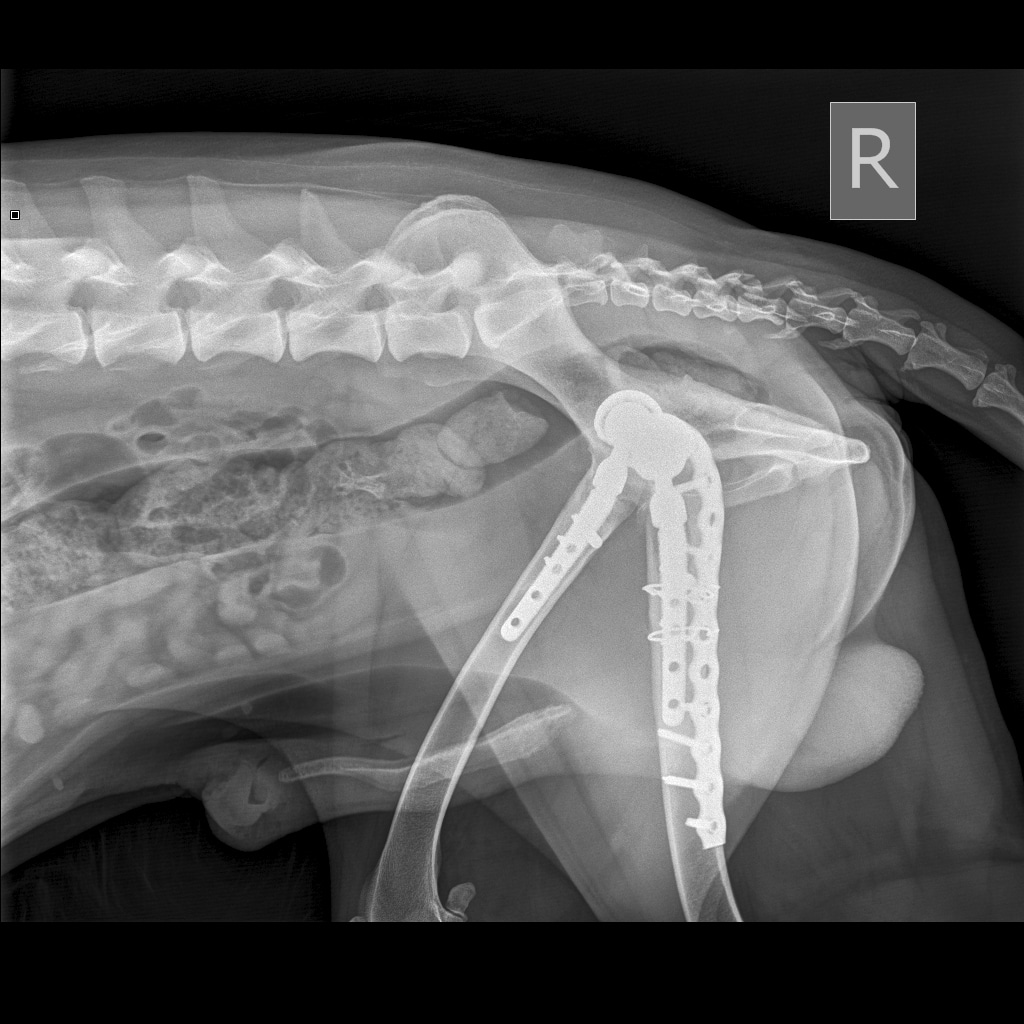

Вчера резко захромал, встал на 3 ноги и понос.

По рентгену чисто

В понедельник КТ